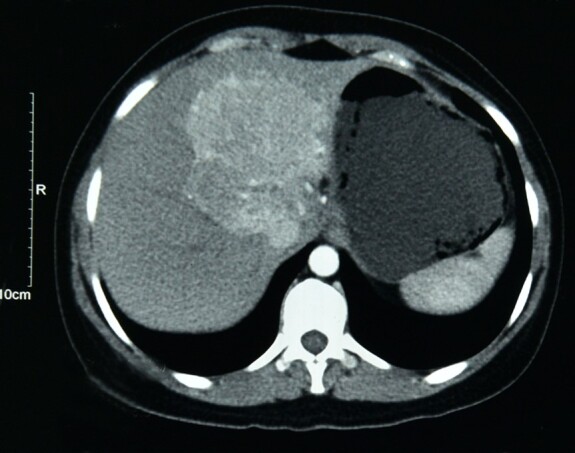

Clear cell myomelanocytic tumor (CCMMT) of the falciform ligament/ligamentum teres is a rare hepatic tumor, a variant of the perivascular epithelioid cell tumor (PEComa) family. CCMMT is the rarest variant of hepatic PEComas. Only a few cases of CCMMT have been reported in the English literature. Because of its rarity, less is known about its biological behavior. We present a case of a 31-year-old female who complained of abdominal pain, bilious vomiting, and abdominal fullness over two months. The radiological impression was of focal nodular hyperplasia. The histological examination of the resection specimen revealed a well-circumscribed tumor arranged in fascicles, sheets, and a whorling pattern. The tumor cells were spindle to epithelioid shaped with abundant clear to pale eosinophilic cytoplasm. The tumor cells expressed both myoid (smooth muscle actin) and melanocytic (MelanA and HMB45) markers, while they were negative for hepatocytic and vascular markers. Thus, based on histology and immunohistochemistry, a diagnosis of CCMMT was made. This case presents the diagnostic challenges of CCMMT and discusses the differential diagnosis with a literature review.